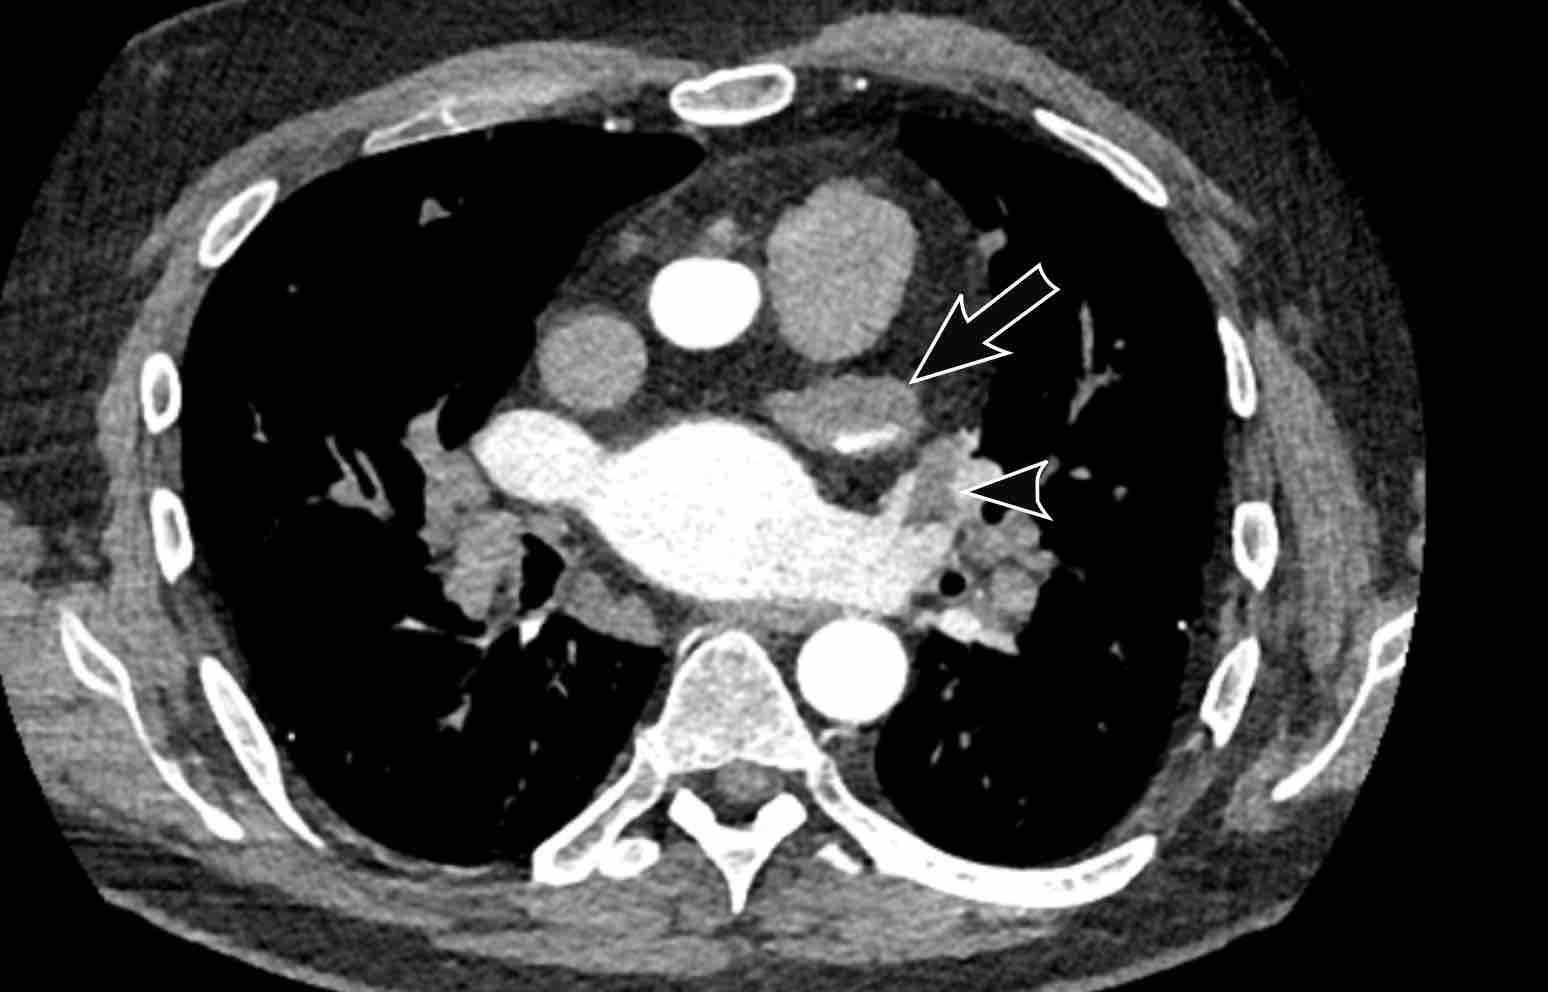

Cuộn qua các hình ảnh của bệnh nhân rung nhĩ.

Nhận xét các phát hiện?

Hình ảnh

Nhĩ trái giãn.

Có huyết khối trong tiểu nhĩ trái (mũi tên) lan rộng về phía nhĩ trái (đầu mũi tên).

Tại tiểu nhĩ trái, thường gặp khó khăn trong chẩn đoán phân biệt hình ảnh giữa huyết khối và hiện tượng ngấm thuốc không hoàn toàn do dòng chảy chậm, đặc biệt khi chụp ở thì thuốc sớm.

Vấn đề này có thể được giải quyết bằng cách chụp CT ở thì thuốc muộn hơn hoặc chụp ở tư thế nằm sấp.

Siêu âm tim qua thực quản được coi là tiêu chuẩn vàng.